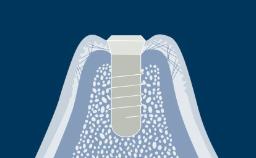

A geometria do corpo dos implantes geralmente pode ser dividida em três partes: a parte endóssea, que se encontra dentro do osso, a seção transmucosa, que fica nos tecidos moles entre o osso e a cavidade oral, e a interface com os componentes protéticos. Em cada uma dessas três partes, existem outras características da geometria e variações na sua forma, atributos e dimensões. Existem também variações no material do corpo do implante e no tratamento de superfície. Essas variações serão descritas e discutidas nos seguintes Objetivos de Aprendizagem.